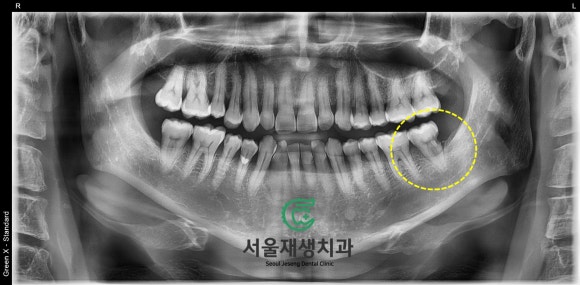

치과 검사의 기본, 파노라마 엑스레이

50대의 나이에도 불구하고

임플란트 하나 하신 적 없는

아주 건강한 치열을 가지신 환자분입니다.

그런데 화면 오른쪽 아래에 있는

어금니에 심상치 않은 소견이

관찰됩니다.

머리와 뿌리 사이에

아슬아슬하게

영토를 확장 중인 충치!

신경까지 확장된 것은 물론이고,

뿌리 방향으로도 내려가고 있습니다.

문제는 얼마나 깊게 내려갔냐인데요..